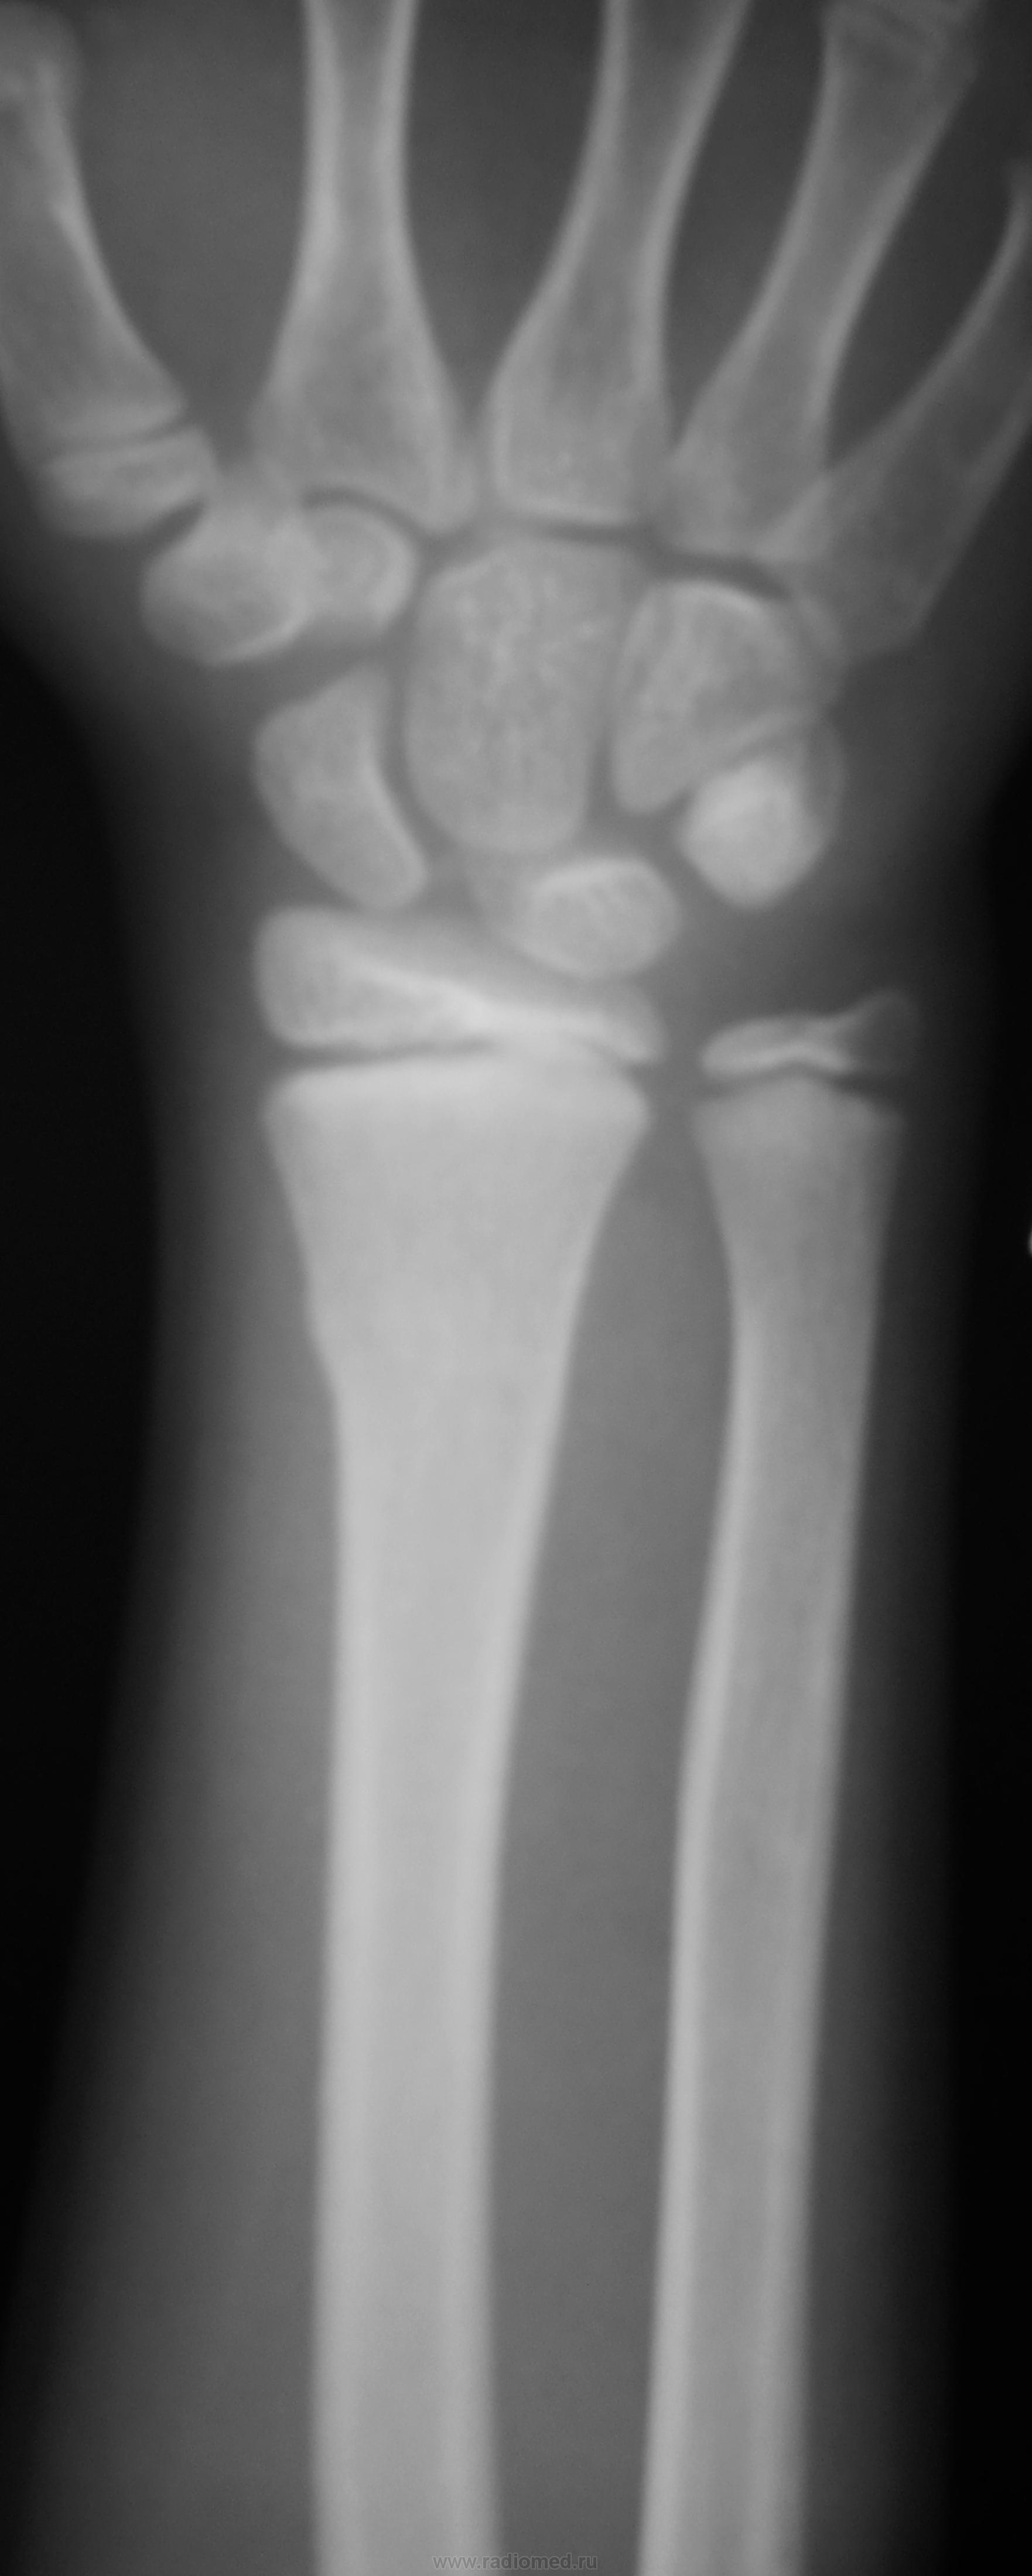

Травма. Пациент направлен на рентгенографию лучезапястного сустава

+ перелом дистального метафиза лучевой кости

поднадкостничный перелом дистального метадиафиза лучевой кости....без смещения отломков...ладьевидная кость так не ломается.)  сверхкомплектная кость...сочетать с клиникой ..с локализацией болезнености.

Поднадкостничный перелом лучевой кости в нижней трети без смещения. Краевой перелом ладьевидной кости? Остеохондропатия ладьевидной кости?

Гипсовый лонгет "на луч". Наблюдение в динамике, рентген-контроль по показаниям.